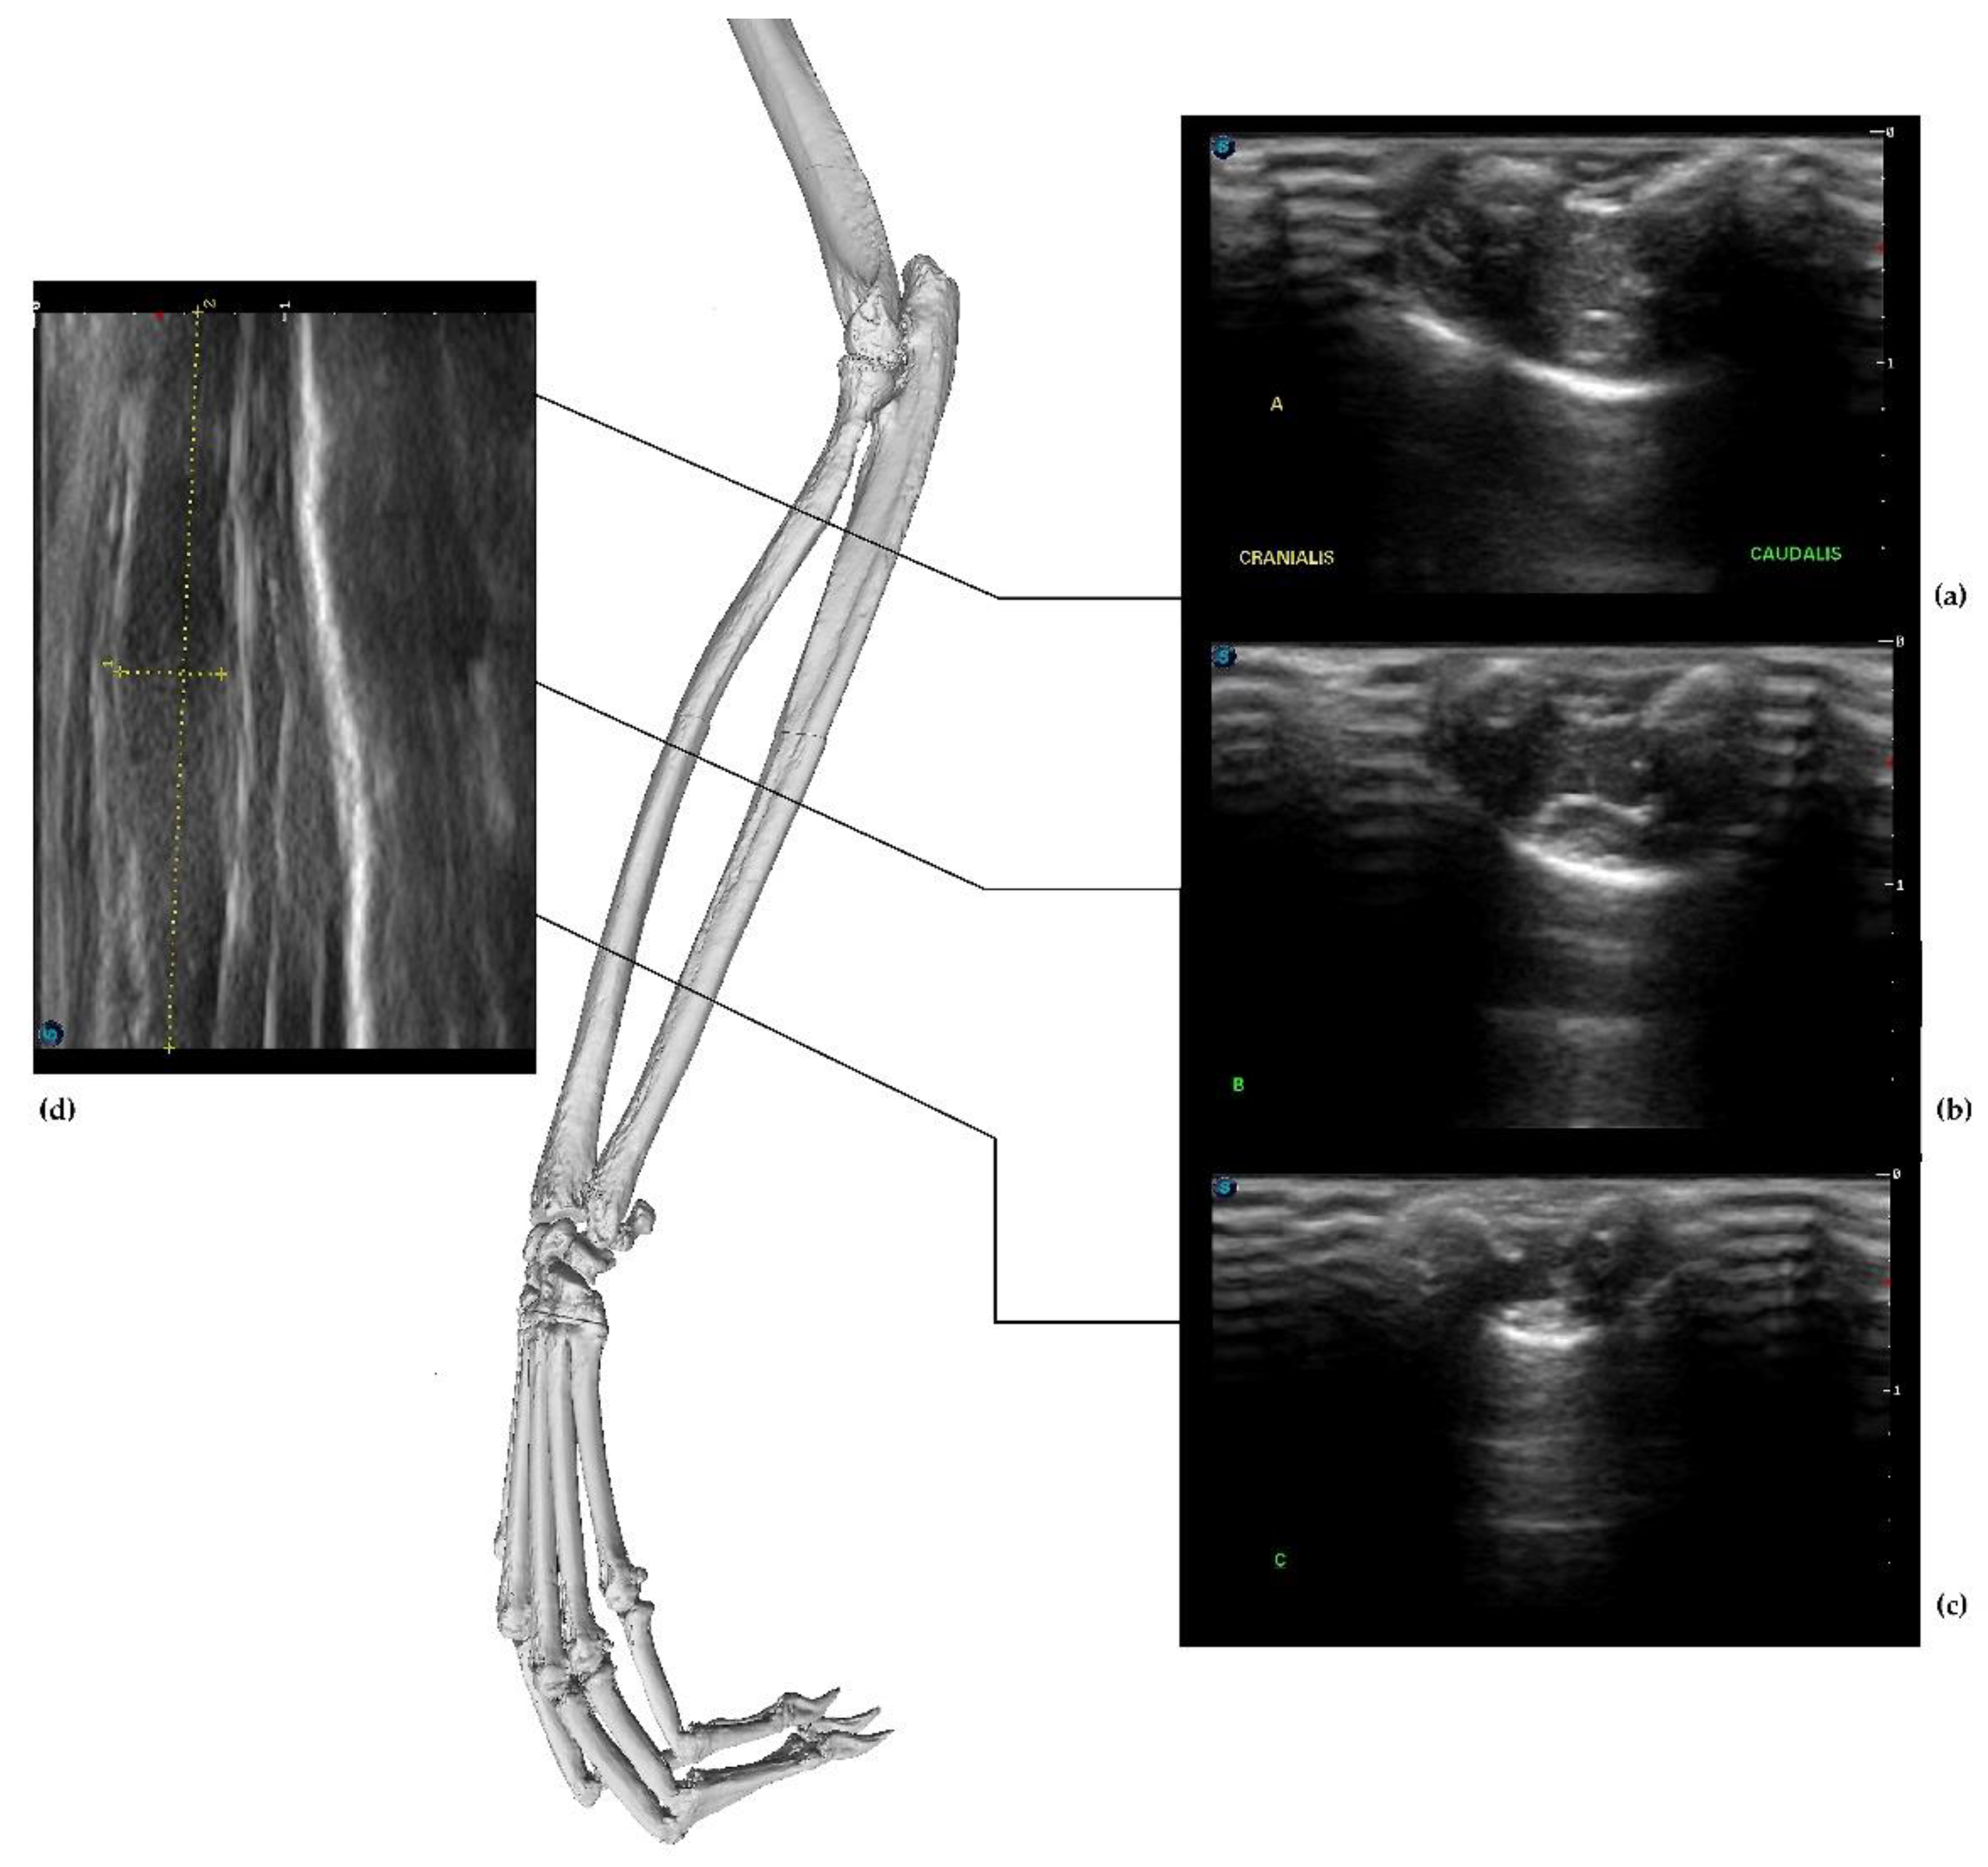

3.2. Ultrasonography Examination

- The radial group included the following muscles: BR, ECRL, and ECRB, which were located at the anterolateral portion of the forearm. US imaging revealed the flat shape and location of the BR muscle belly, which was visible only in a cross-section. The ECRL and ECRB were located at the posterolateral portion of the forearm. They were more cylindrical and elongated. The supinator muscle was not visible in the figure;

- The superficial dorsal group included the EDC and EDM, located at the lateral portion of the forearm;

- The ulnar group was shown with the main visible muscle—the ECU—located at the caudal surface of the forearm from the lateral epicondyle of the humerus. The belly was well visible because of its cylindrical shape. The SDF located at the caudomedial portion of the forearm was the last muscle in this group;

- The deep medial group included the APL, which originated from the interosseous membrane and passed through the wrist as a small tendon. The EPB was not detected. The main mass of the group was represented by the DDF;

- The pronator group included the PT and PQ muscles.